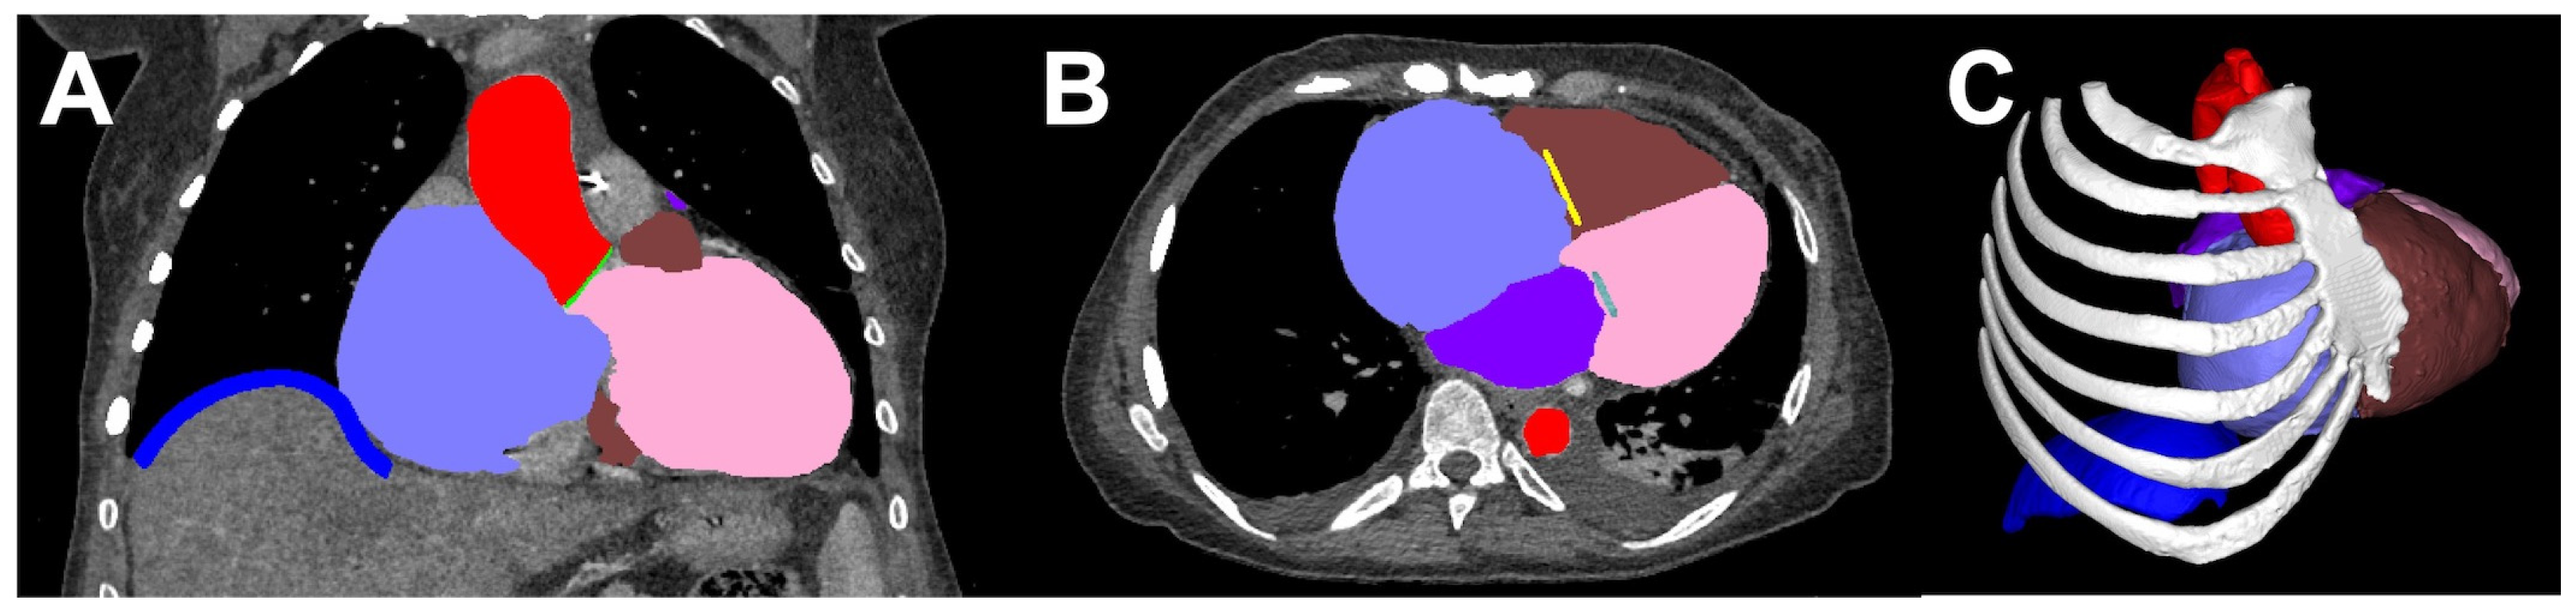

- Bertolini, M.; Rossoni, M.; Colombo, G. Operative Workflow from CT to 3D Printing of the Heart: Opportunities and Challenges. Bioengineering 2021, 8, 130. [Google Scholar] [CrossRef]

- Abudayyeh, I.; Gordon, B.; Ansari, M.M.; Jutzy, K.; Stoletniy, L.; Hilliard, A. A practical guide to cardiovascular 3D printing in clinical practice: Overview and examples. J. Interv. Cardiol. 2017, 31, 375–383. [Google Scholar] [CrossRef]